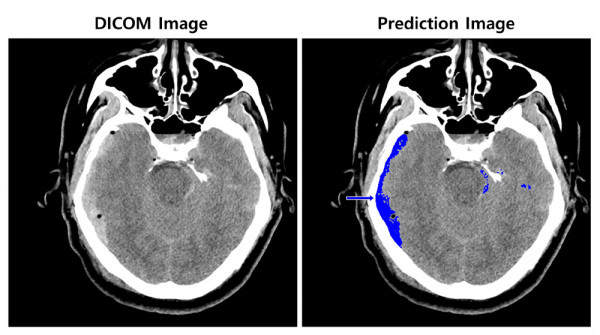

Phổ biến công nghệ đọc hình ảnh xuất huyết não bằng AI tại Hàn Quốc ảnh 1Ảnh minh họa. (Nguồn: koreaittimes.com)

Giải pháp này do công ty phát triển, phân tích hình ảnh chụp cắt lớp vi tính (CT) não trong vòng vài giây với AI, thông báo cho nhân viên y tế về vị trí chảy máu và bất kỳ bất thường nào với độ chính xác hơn 97%.